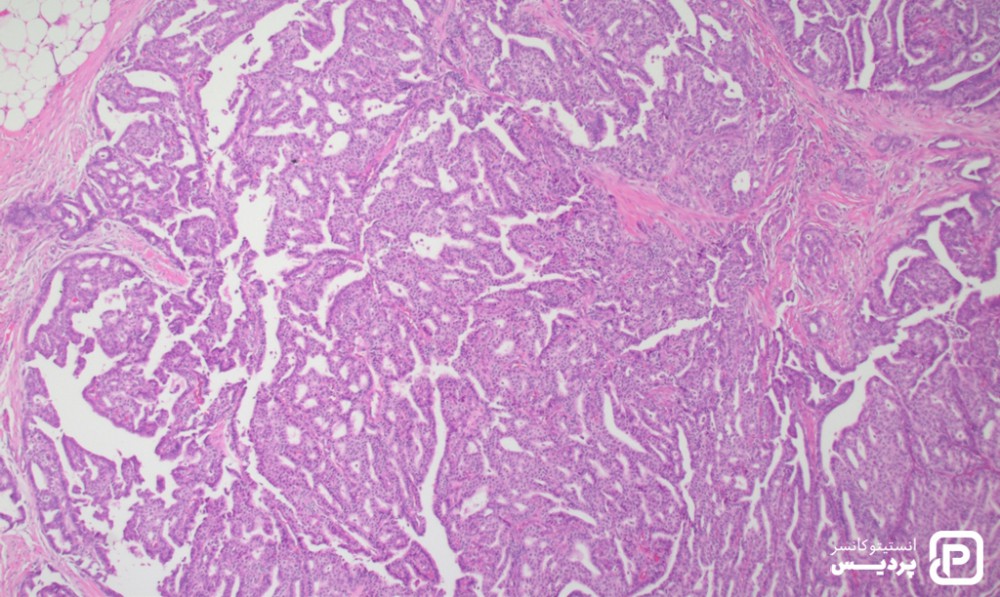

در کارسینوم پاپیلاری، سلول های سرطانی به شکل و الگوی خاص سرخس مانند در زیر میکروسکوپ ظاهر می شوند. کارسینوم پاپیلاری از انواع نادر سرطان پستان است که حدود 3 درصد از کل سرطان های پستان را شامل می شود. این نوع سرطان معمولاً پیش آگهی بهتری نسبت به سایر سرطان های شایع پستان دارد. تفاوت اصلی کارسینوم پاپیلاری و سایر سرطان های سینه، شکل ظاهری سلول های سرطانی است که طبق الگوی خاصی زیر میکروسکوپ دیده می شوند. برخی اوقات، سلول های سرطانی بسیار کوچک هستند. در این حالت ممکن است سرطان را میکروپاپیلاری بنامند.

اغلب کارسینوم پاپیلاری پستان تهاجمی هستند و مانند کارسینوم داکتال تهاجمی درمان می شوند. با این حال، کارسینوم پاپیلاری تهاجمی پیش آگهی بهتری نسبت به سایر سرطان پستان تهاجمی دارد. اغلب اوقات، کارسینوم پاپیلاری تهاجمی پس از گسترش کارسینوم پاپیلاری غیرتهاجمی رخ می دهد.

کارسینوم پاپیلاری ممکن است هنگامی که غیرتهاجمی است، تشخیص داده شود. کارسینوم پاپیلاری غیرتهاجمی معمولاً نوعی از کارسینوم داکتال درجا محسوب می شود. در مراحل ابتدایی، هنگامی که سلول های سرطانی تازه شروع به تحت تأثیر قرار دادن مجاری کرده اند، این بیماری ممکن است به عنوان کارسینوم پاپیلاری infiltrating یاد شود. درمان کارسینوم پاپیلاری اغلب ترکیبی از روش های جراحی، رادیوتراپی، شیمی درمانی، هورمون درمانی یا نوعی از درمان است که پروتئین HER2 را هدف قرار می دهد.